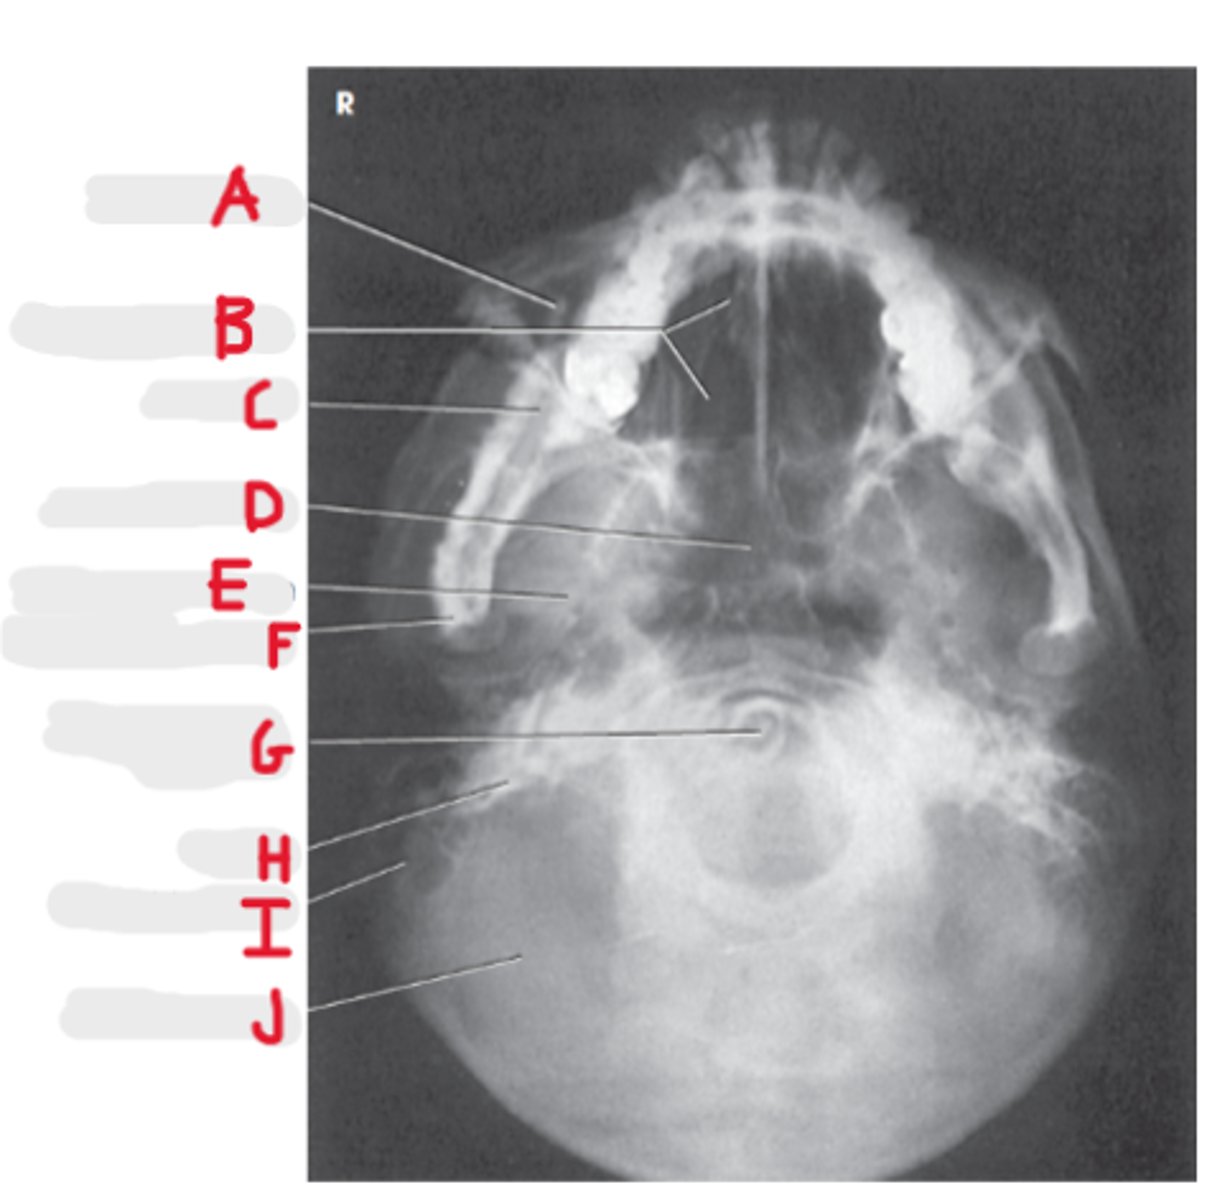

Submentovertex (or vertical) SMV

What projection is this?

CR - perpendicular to IOML

enters 1-1 1/2 inch below the mentum

What is the CR for the SMV?

Infraorbital meatal line (IOML)

What line is parallel to the IR for the SMV?

Basal view because it demonstrates the base of the skull

What is the SMV known as and why?

Sphenoid and ethmoid

What sinuses are best demonstrated on an SMV?

Look for equidistant lateral border of skull to mandibular condyles

How do we look for rotation/tilt on an SMV radiograph?

Maxillary sinus

A

Ethmoid air cells

B

Mandible

C

Sphenoid Sinus

D

Foramen spinosum

E

Mandibular condyle

F

Dens or odontoid process

G

Petrosa

H

Mastoid process

I

Occipital bone

J